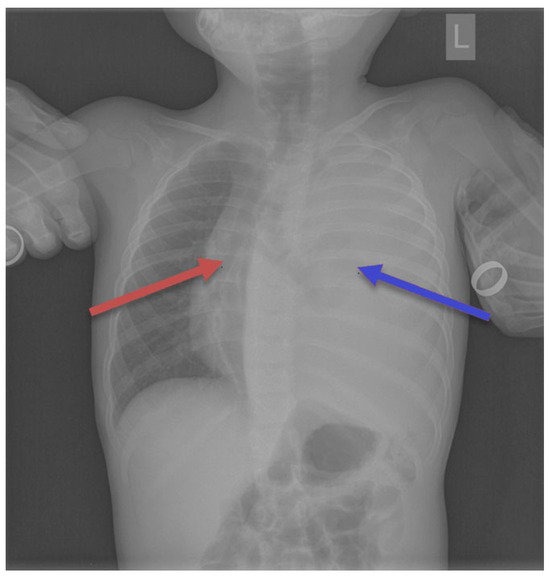

3.2. Diagnosis

3.3. Symptoms and Signs

3.4. Tumor Localization and Size